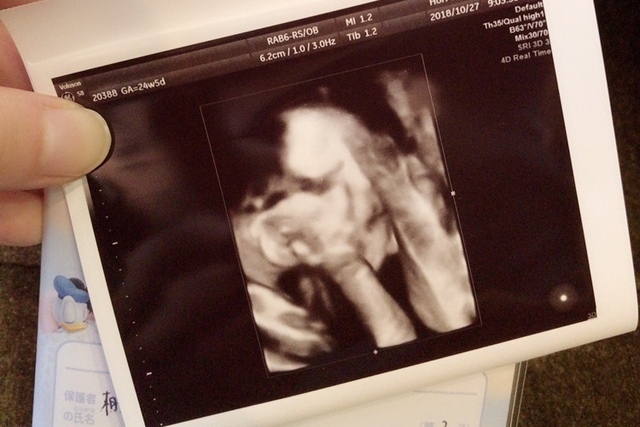

24週4日(24w4d・男の子)|mayu_28 さん(29歳)

エコー写真撮影時のエピソード:

悪阻がなく、妊娠前同様もりもり食事をしていました。初めてのエコー写真の時には既に男の子かもと判明。この写真の時はパパが一緒に付き添いでした。パパがいるとこんなに上手に顔を出してくれます。パパがお仕事から帰ってくるとわかるのか、とても喜んで動いたり、声かけに反応しているようでお腹の中にいる時がパパ好きで嬉しいです!